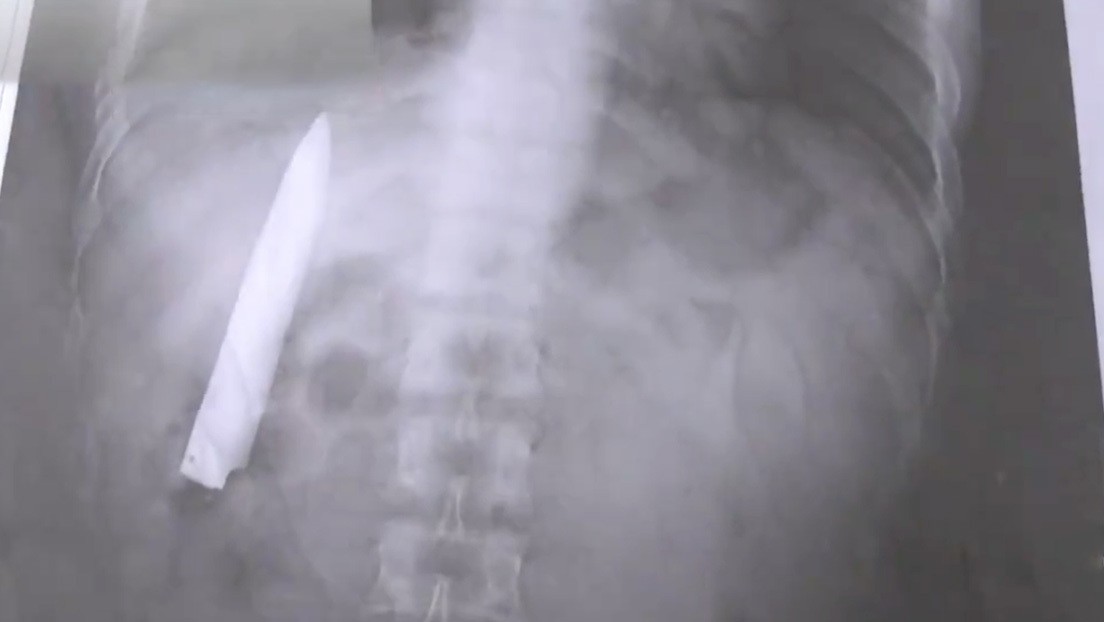

Es que en pruebas de rayos x descubrieron que seguía teniendo en el torso la hoja de un cuchillo.

"Siempre me pregunté por qué siento algo de dolor en mi pecho cuando el clima es frío, pero no tenía idea de que un cuchillo seguía ahí", comentó el hombre.